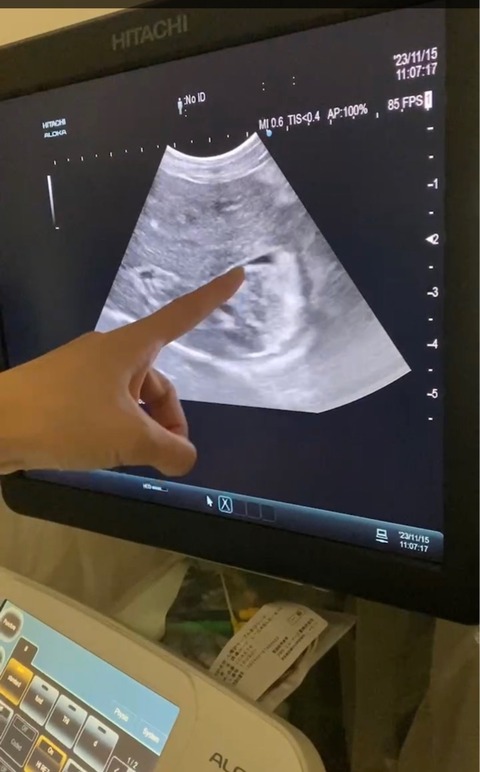

VIVIちゃんはエコー検査になりました、

胆泥が溜まっているそうです💦

胆嚢が汚れているそうです